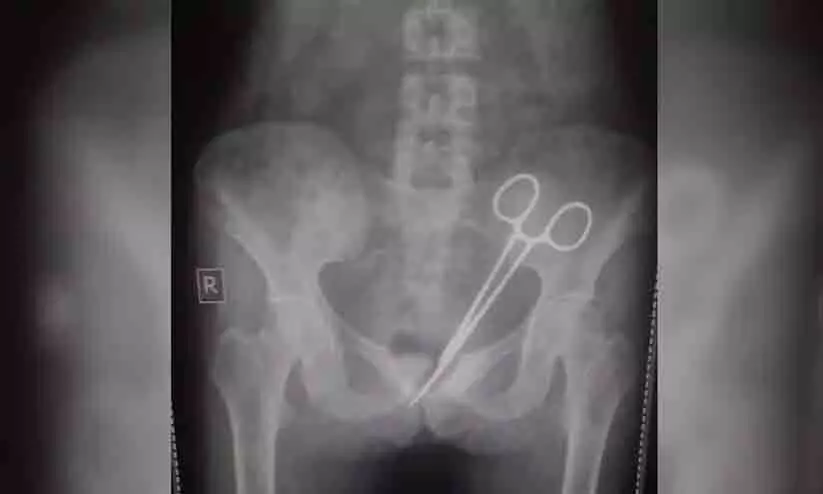

നിരവധി ഡോക്ടർമാർ പരിശോധിച്ചിട്ടും കാരണം കണ്ടെത്താൻ സാധിച്ചില്ല. ഒടുവിൽ ഈ മാസാദ്യം നടത്തിയ എക്സ് റേ പരിശോധനയിലാണ് 45കാരിയുടെ വയറ്റിൽ കത്രിക കണ്ടെത്തിയത്.

2012ൽ സിക്കിമിലെ സർ തുതുതോബ് നംഗ്യാൽ സ്മാരക ആശുപത്രിയിൽ വെച്ചാണ് യുവതിക്ക് അപ്പന്റിക്സിന് ശസ്ത്രക്രിയ നടത്തിയത്. അന്ന് ഡോക്ടർമാർ വയറ്റിൽ വെച്ച് മറന്നതായിരുന്നു അത്. അതിനു ശേഷവും വയറുവേദന ഭേദമായില്ല. പല ഡോക്ടർമാരെ കണ്ടിട്ടും ഫലമുണ്ടായില്ലെന്ന് യുവതിയുടെ ഭർത്താവ് പറയുന്നു.

ഒക്ടോബർ എട്ടിന് മുമ്പ് ശസ്ത്രക്രിയ നടത്തിയ ആശുപത്രിയിൽ വീണ്ടും ചെന്നപ്പോൾ എക്സ്റേ എടുക്കുകയായിരുന്നു. അപ്പോഴാണ് ശസ്ത്രക്രിയ ഉപകരണം വയറ്റിൽ വെച്ച് മറന്ന കാര്യം ഡോക്ർമാർ അറിയുന്നത്. ഉടൻ തന്നെ വിദഗ്ധ ഡോക്ടർമാരുടെ നേതൃത്വത്തിൽ വീണ്ടും ശസ്ത്രക്രിയ നടത്തി കത്രിക പുറത്തെടുത്തു. വാർത്ത പുറത്തുവന്നതോടെ ആശുപത്രിക്കെതിരെ വലിയ പ്രതിഷേധമാണ് ഉയരുന്നത്. സംഭവത്തിൽ അന്വേഷണം പ്രഖ്യാപിച്ചിട്ടുണ്ട്.